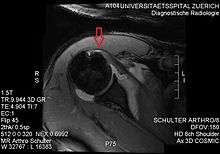

Imaging

Although the subscapularis is the major and most powerful muscle of the rotator cuff and has an enormous meaning in the gleno-humeral stability and dynamic it is neglected in the clinical literature. Despite its importance and impact on conservative or surgical treatment, operative planning and approach or post-surgical prognosis. Lo and Burkhart even tagged the subscapularis tendon hypercritically as the "forgotten tendon". That arises by the gap of the described tear prevalence in cadavers between 29 and 37% and in clinical studies around 27%. This is likely related to the difficulties in radiological, arthroscopic and even open surgical assessment of this particular muscle and its tendon, especially for inferior tears. For example, even full-thickness tears can be mimicked by intact tendon fibers or overlying scars attached to the greater tuberosity. Since the strong stabilizing effect of the coraco-humeral ligament a possible muscle retraction can be expeditiously underestimated. Scar tissue can be adulterant for MR Arthrographic images, as it may prevent leakage of contrast material.

There is no singularly imaging device or technique for a satisfying and complete subscapularis examination, but rather the combination of the sagittal oblique MRI / short-axis US and axial MRI / long-axis US planes seems to generate useful results. Additionally lesser tuberosity bony changes have been associated with subscapularis tendon tears. Findings with cysts seem to be more specific and combined findings with cortical irregularities more sensitive.[3]